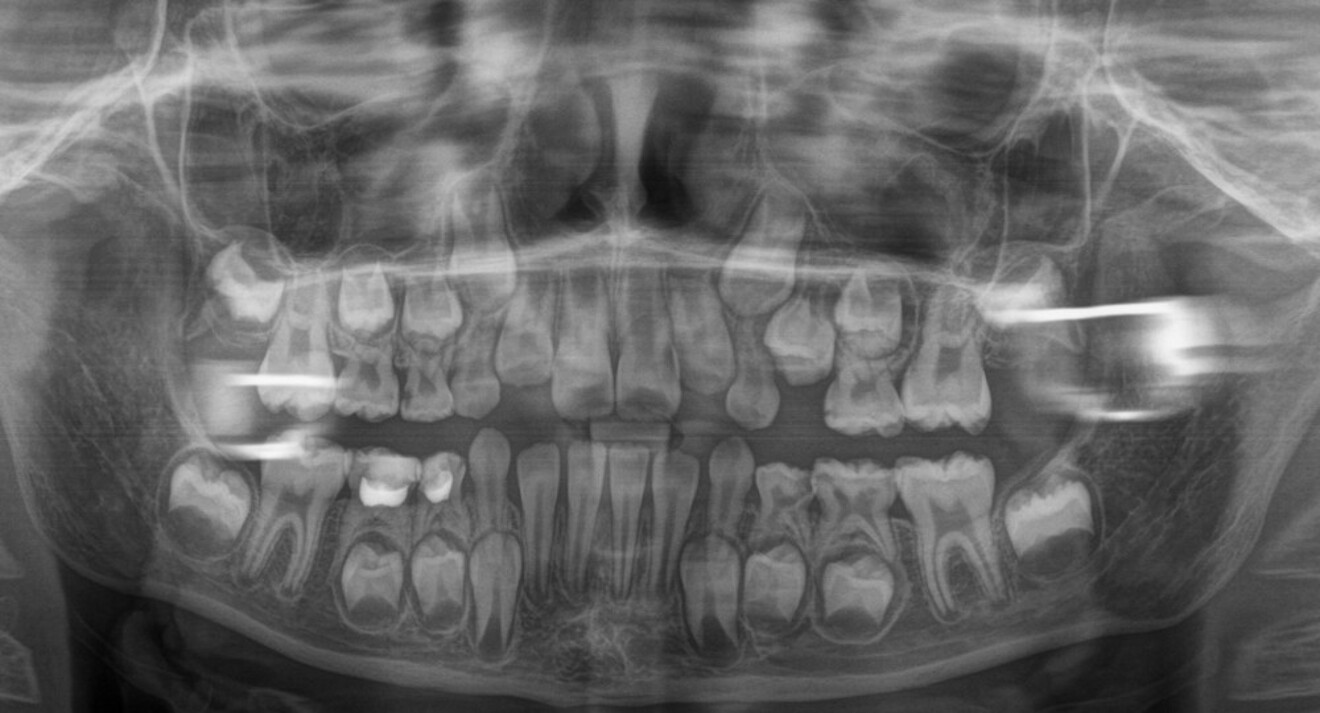

Fig. 4a: Pre-treatment panoramic radiograph.